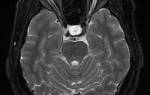

Зрительный нерв

Диск зрительного нерва находится в носовой половине сетчатки, в 2-3 мм медиальнее заднего полюса глаза и на 0,5-1,0 мм книзу от него. Форма его округлая или овальная, слегка вытянутая в вертикальном направлении. Диаметр диска — 1,75-2,0 мм. В месте расположения диска зрительных нейронов нет, поэтому в височной половине поля зрения каждого глаза диску зрительного нерва соответствует физиологическая скотома, известная как слепое пятно. Впервые оно было описано в 1668 г. физиком Э. Мариоттом.

Диск зрительного нерва снизу, сверху и с назальной стороны несколько выступает над уровнем окружающих его структур сетчатой оболочки, а с височной стороны находится на одном с ними уровне. Это связано с тем, что сходящиеся с трех сторон нервные волокна в процессе образования диска делают небольшой изгиб в сторону стекловидного тела.

По краю диска с трех сторон образуется небольшой валик, а в центре диска — воронкообразное углубление, известное как физиологическая экскавация диска, глубиной около 1 мм. Через него проходят центральная артерия и центральная вена сетчатки. С височной стороны диска зрительного нерва такой валик отсутствует, так как вступающий здесь в его состав папилломакулярный пучок, состоящий из нервных волокон, отходящих от ганглиозных нейронов, расположенных в желтом пятне сетчатки, сразу же, почти под прямым углом, погружается в склеральный канал. Выше и ниже папилломакулярного пучка в диске зрительного нерва находятся нервные волокна, идущие, соответственно, от верхнего и нижнего квадрантов височной половины сетчатки. Медиальную часть диска зрительного нерва составляют аксоны ганглиозных клеток, расположенные в медиальной (носовой) половине сетчатой оболочки.

Внешний вид диска зрительного нерва и размер его физиологической экскавации зависит от особенностей склерального канала и угла, под которым этот канал расположен по отношению к глазу. Четкость границ диска зрительного нерва определяется особенностями входа зрительного нерва в склеральный канал.